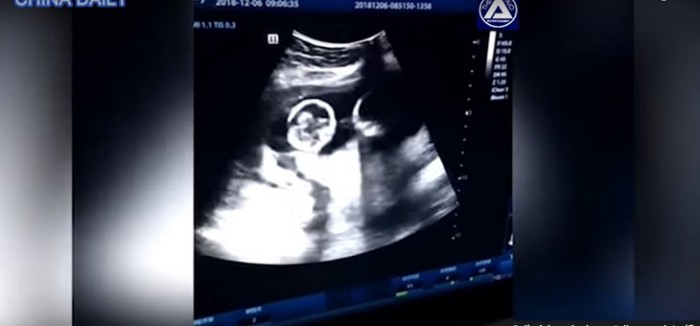

Gemelas son captadas peleando en el útero de su madre

Un curioso video está dando la vuelta al mundo. Se trata una ecografía, que muestra la pelea entre unas gemelas al interior del útero de su madre, que ya acumula más de 2,5 millones de reproducciones.

El curioso hecho ocurrió en Yinchuan, China, durante un control rutinario, a los cuatro meses de gestación, según consigna el diario inglés Daily Mail. La escena de las niñas, que parecen estar boxeando, llamó la atención del padre, que filmó la secuencia y la subió a Internet, donde registra cerca de 80 mil comentarios.